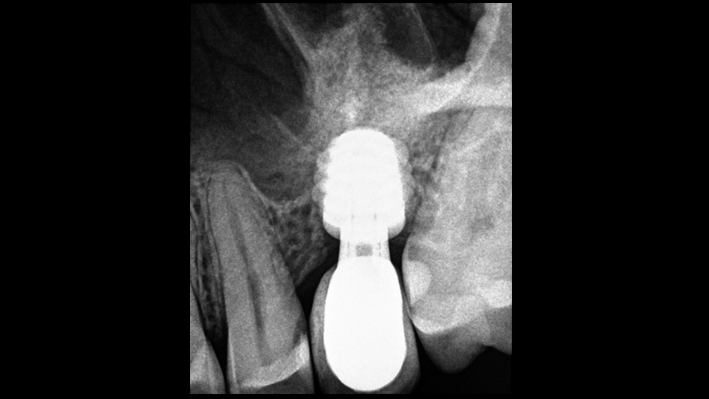

Klinik vaka: # 46 implant yerleştirilmesi & i-Gen membran kullanılarak belirgin vertikal rezorpsiyon & miks kemik defekti için GBR

- Dr. Iulian Filipov (Romanya) katkılarıyla -

Anahtar Kelimeler

AnyRidge, mandibular posterior, i-Gen, rezorpsiyon, kemik defekti, kemik rejenerasyonu, boşluk yönetimi, #46, GBR, Dr. Iulian Filipov